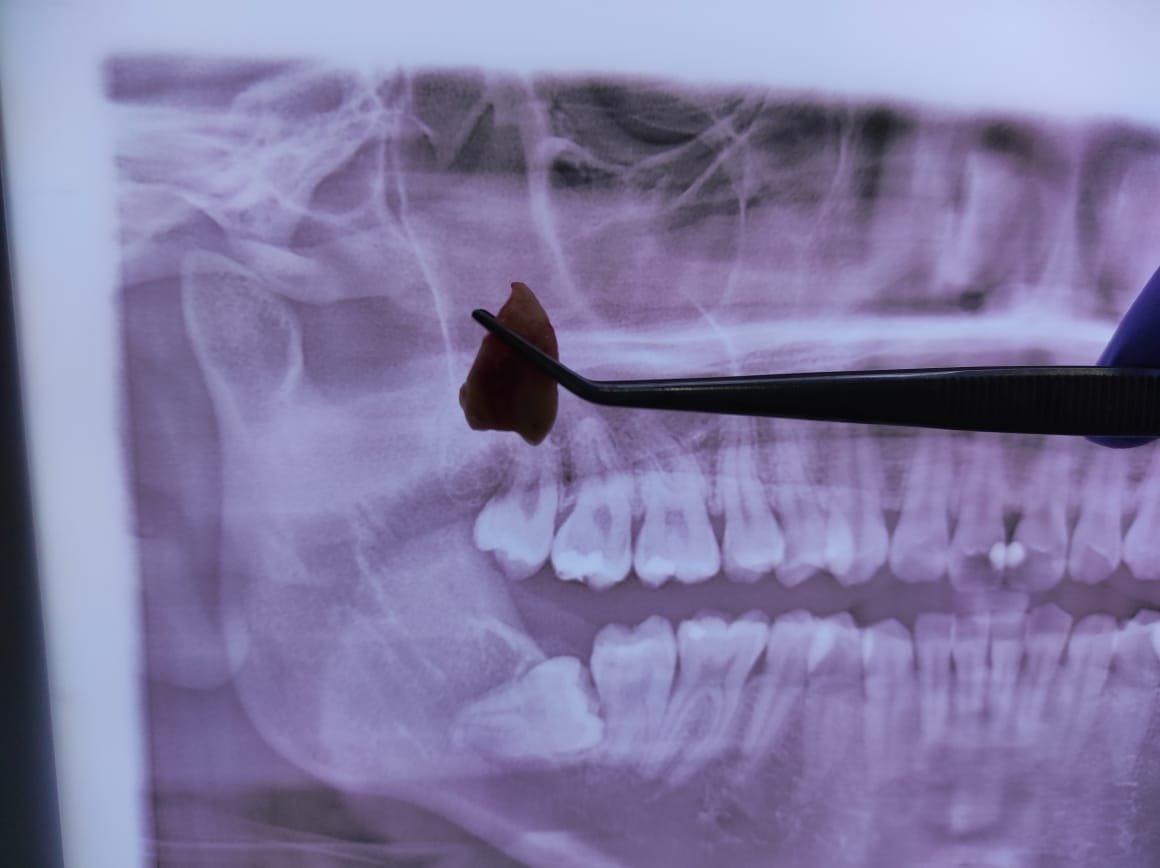

1. Pemeriksaan awal

Dokter melakukan rontgen panoramic untuk melihat posisi gigi bungsu dan menilai kondisi pasien.